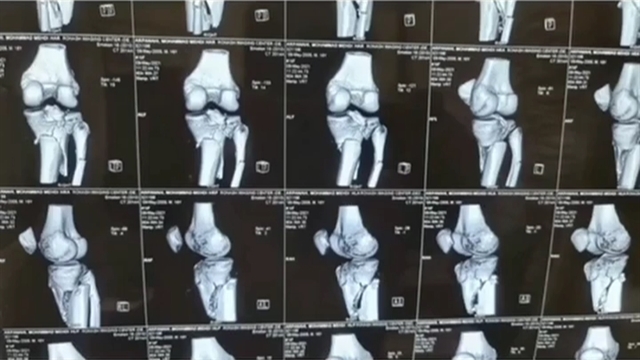

خردشدگی شدید زانو

خردشدگی شدید زانو‌